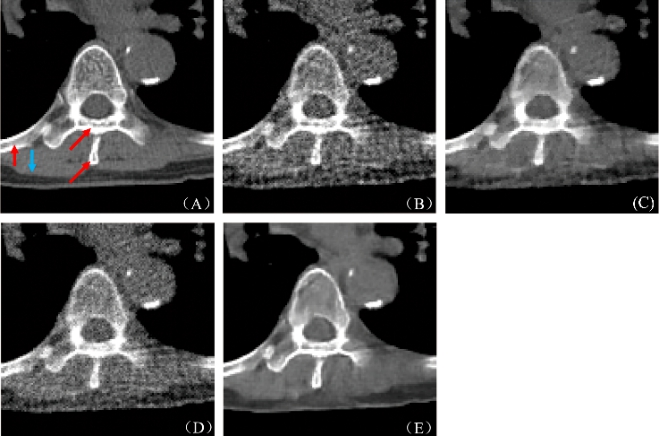

图2:重建结果. (A) 参考图像, (B) FBP重建结果, (C) PWLS-TGV重建结果, (D) R-NLTV重建结果, (E) DD-Net重建结果

图3:图2(A)中红色标记局部区域的放大图(A) 参考图像, (B) FBP重建结果, (C) PWLS-TGV重建结果, (D) R-NLTV重建结果, (E) DD-Net重建结果